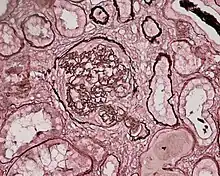

Glomerulonefrites ou glomerulopatias são afecções que acometem o glomérulo, estruturas microscópicas do rim formadas por um emaranhado de capilares e que é a principal estrutura renal responsável pela filtração do sangue.

Histologicamente, são classificadas em várias entidades, uma vez que a glomerulonefrite pode ter diversas apresentações clínicas. Raramente essas patologias evoluem para insuficiência renal terminal em questão de semanas, geralmente sua evolução é mais lenta e pode demorar meses ou até anos. Quando ocorre piora da função renal em poucas semanas, elas são classificadas como glomerulonefrites rapidamente progressivas, independentemente do tipo histológico.

Considerando todos os glomérulos presentes no tecido renal temos os seguintes termos:

- Lesão difusa: 50% ou mais dos os glomérulos do rim estão acometidos.

- Lesão focal: Menos de 50 % dos glomérulos estão acometidos.

Considerando apenas um glomérulo temos:

- Lesão segmentar: ocorre quando parte ou segmento do glomérulo está acometido.

- Lesão global: todo o tufo capilar de um glomérulo está lesado.